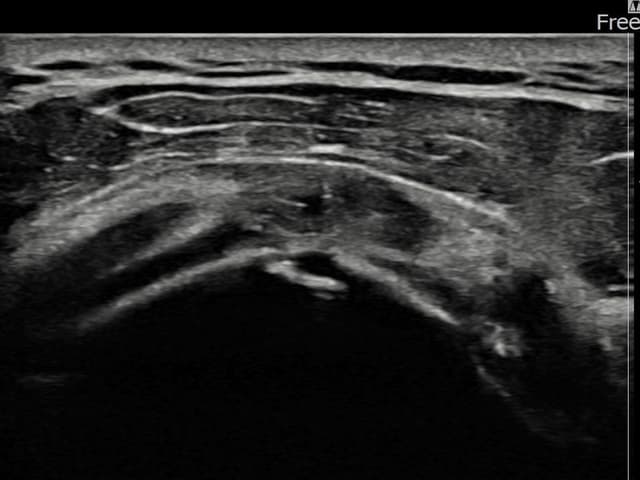

[촬영시기:23.07.31~23.09.27]

[어깨인대 축소봉합술] 좌측 어깨 극상근건 광범위 파열로 수개월간 일상생활이 어렵던 중 내원하셨습니다.